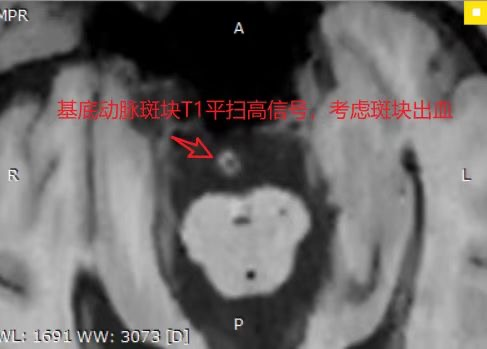

据悉,高分辨磁共振血管壁成像(HRMR-VWI)是近年来发展起来的MRI成像新技术,不仅能评估管腔狭窄程度,还能清晰显示血管壁、动脉粥样硬化斑块及周围结构,分析斑块成分和特征、是否为易损斑块,还能对动脉夹层、血管炎、动脉瘤等疾病进行鉴别诊断,为医生提供更清晰、详细的血管结构图像,也为患者带来了更加个体化、有效的治疗方案。

传统的血管成像方式如MRA、CTA、DSA等主要观察管腔狭窄的情况,不能观察血管壁的具体情况。超声检查可以明确血管内斑块的存在,但对斑块具体成分显示不佳。

高分辨磁共振血管壁成像(HRMR-VWI)技术弥补了传统影像学检查在颅颈部血管疾病的不足,让医生们对管壁精细变化有更直观的了解。该技术具有无创、无辐射、高软组织分辨率、高空间分辨率、高信噪比等优势,已于2019年列入了《中国脑血管病影像指导规范》。